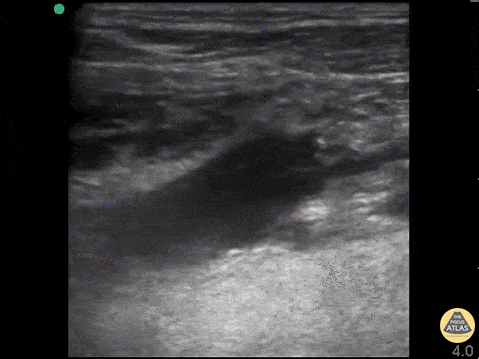

76 y/o M with DOE, no hx of CHF, no signs of infection, smoking hx. What is the finding AND Likely diagnosis after seeing this scan of the Left lung base:

Septated pleural effusion likely exudative, Suspected malignancy